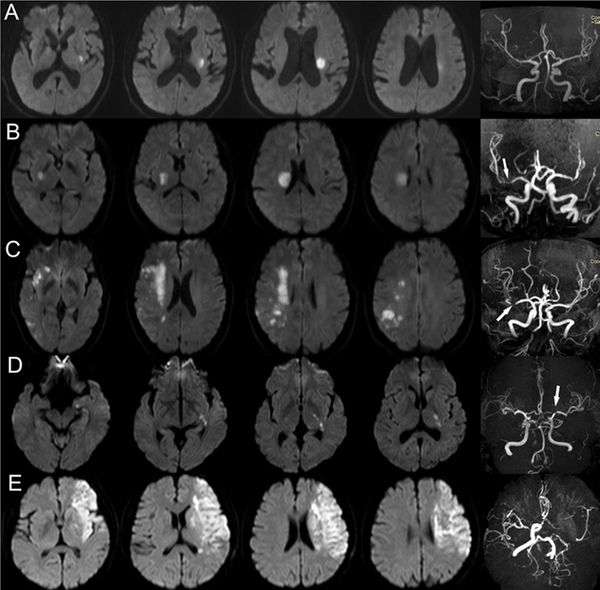

- 緊急磁力共振MRI造影對於在中風黃金小時內進行準確診斷至關重要,尤其是對於缺血性中風。

- MRI 可提供腦部及其血管的詳細影像,從而評估中風類型。

- MRI 亦可顯示缺血性中風時血管阻塞的部位和範圍,或出血性中風時出血的部位和範圍,從而提供選擇合適治療方案的指導。